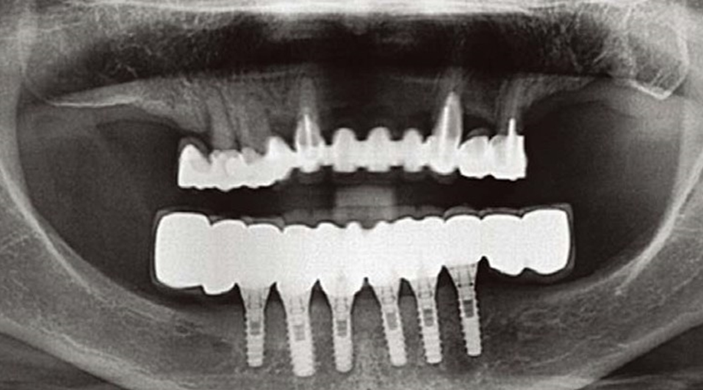

Clinical case: Full-mouth implants for mandibular & maxilla - restored using mixed prostheses

- Courtesy of Dr. Hyun Jun Kim, Korea -

Keywords

AnyRidge, full-mouth implants, mandibular, maxilla, edentulous, full mouth rehabilitation, Octa abutment, long-term clinical case, biological stability, Dr. Hyung Jun Kim

Products:

AnyRidge implant system